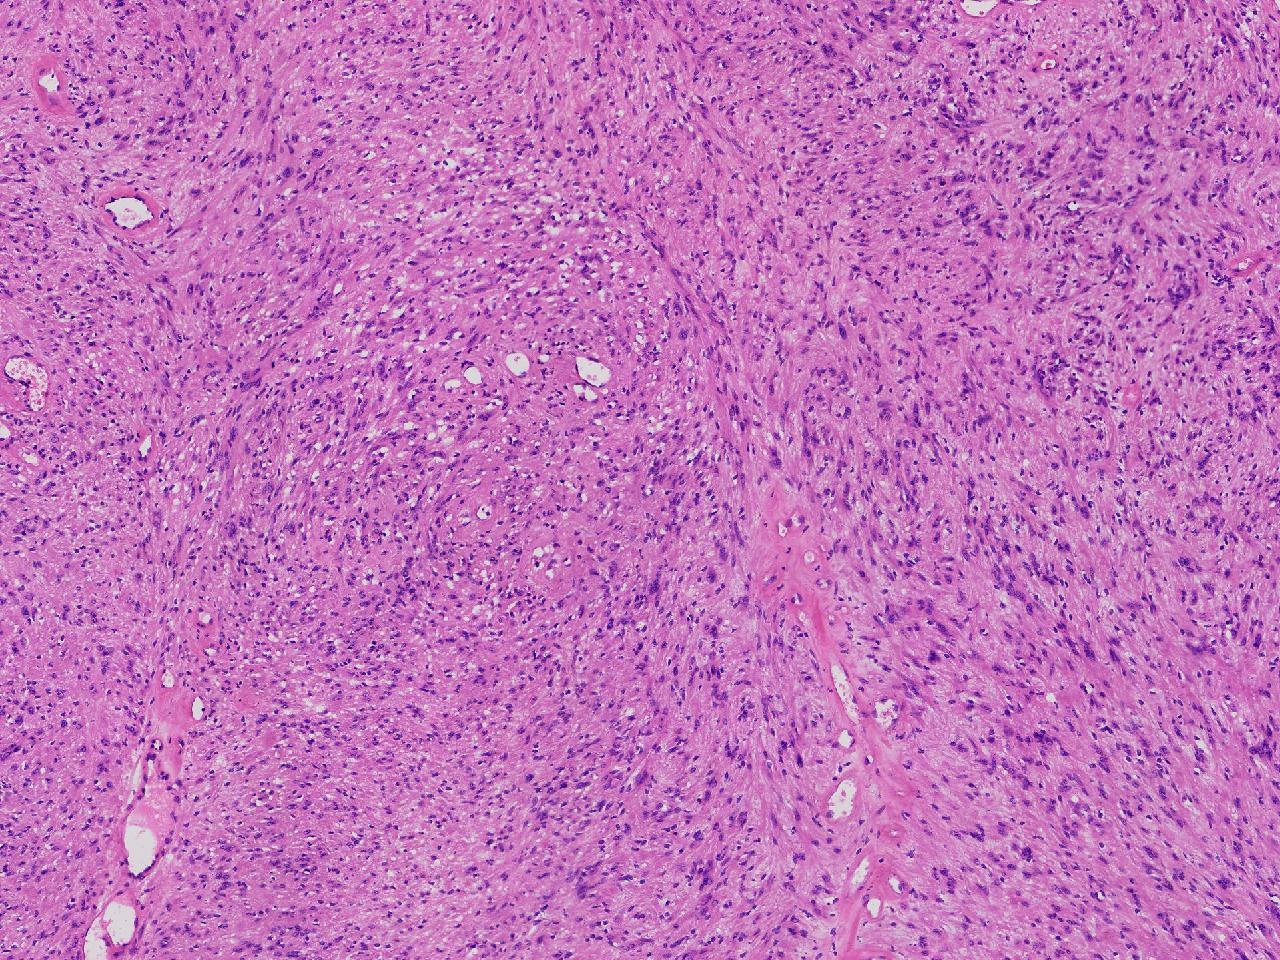

血管平滑肌瘤? 其他?

性别

女

年龄

76岁

临床诊断

右侧腰臀部皮下肿物

一般病史

右侧腰臀部皮下肿物1年余,无明显不适,逐渐增大。

标本名称

大体所见

卵圆形肿物一个,直径1.6厘米,上附皮肤。肿物切面灰黄实性,质中等。

考虑:结节性筋膜炎

神经鞘瘤。

建议除外平滑肌瘤,做IHC是更好的鉴别方式